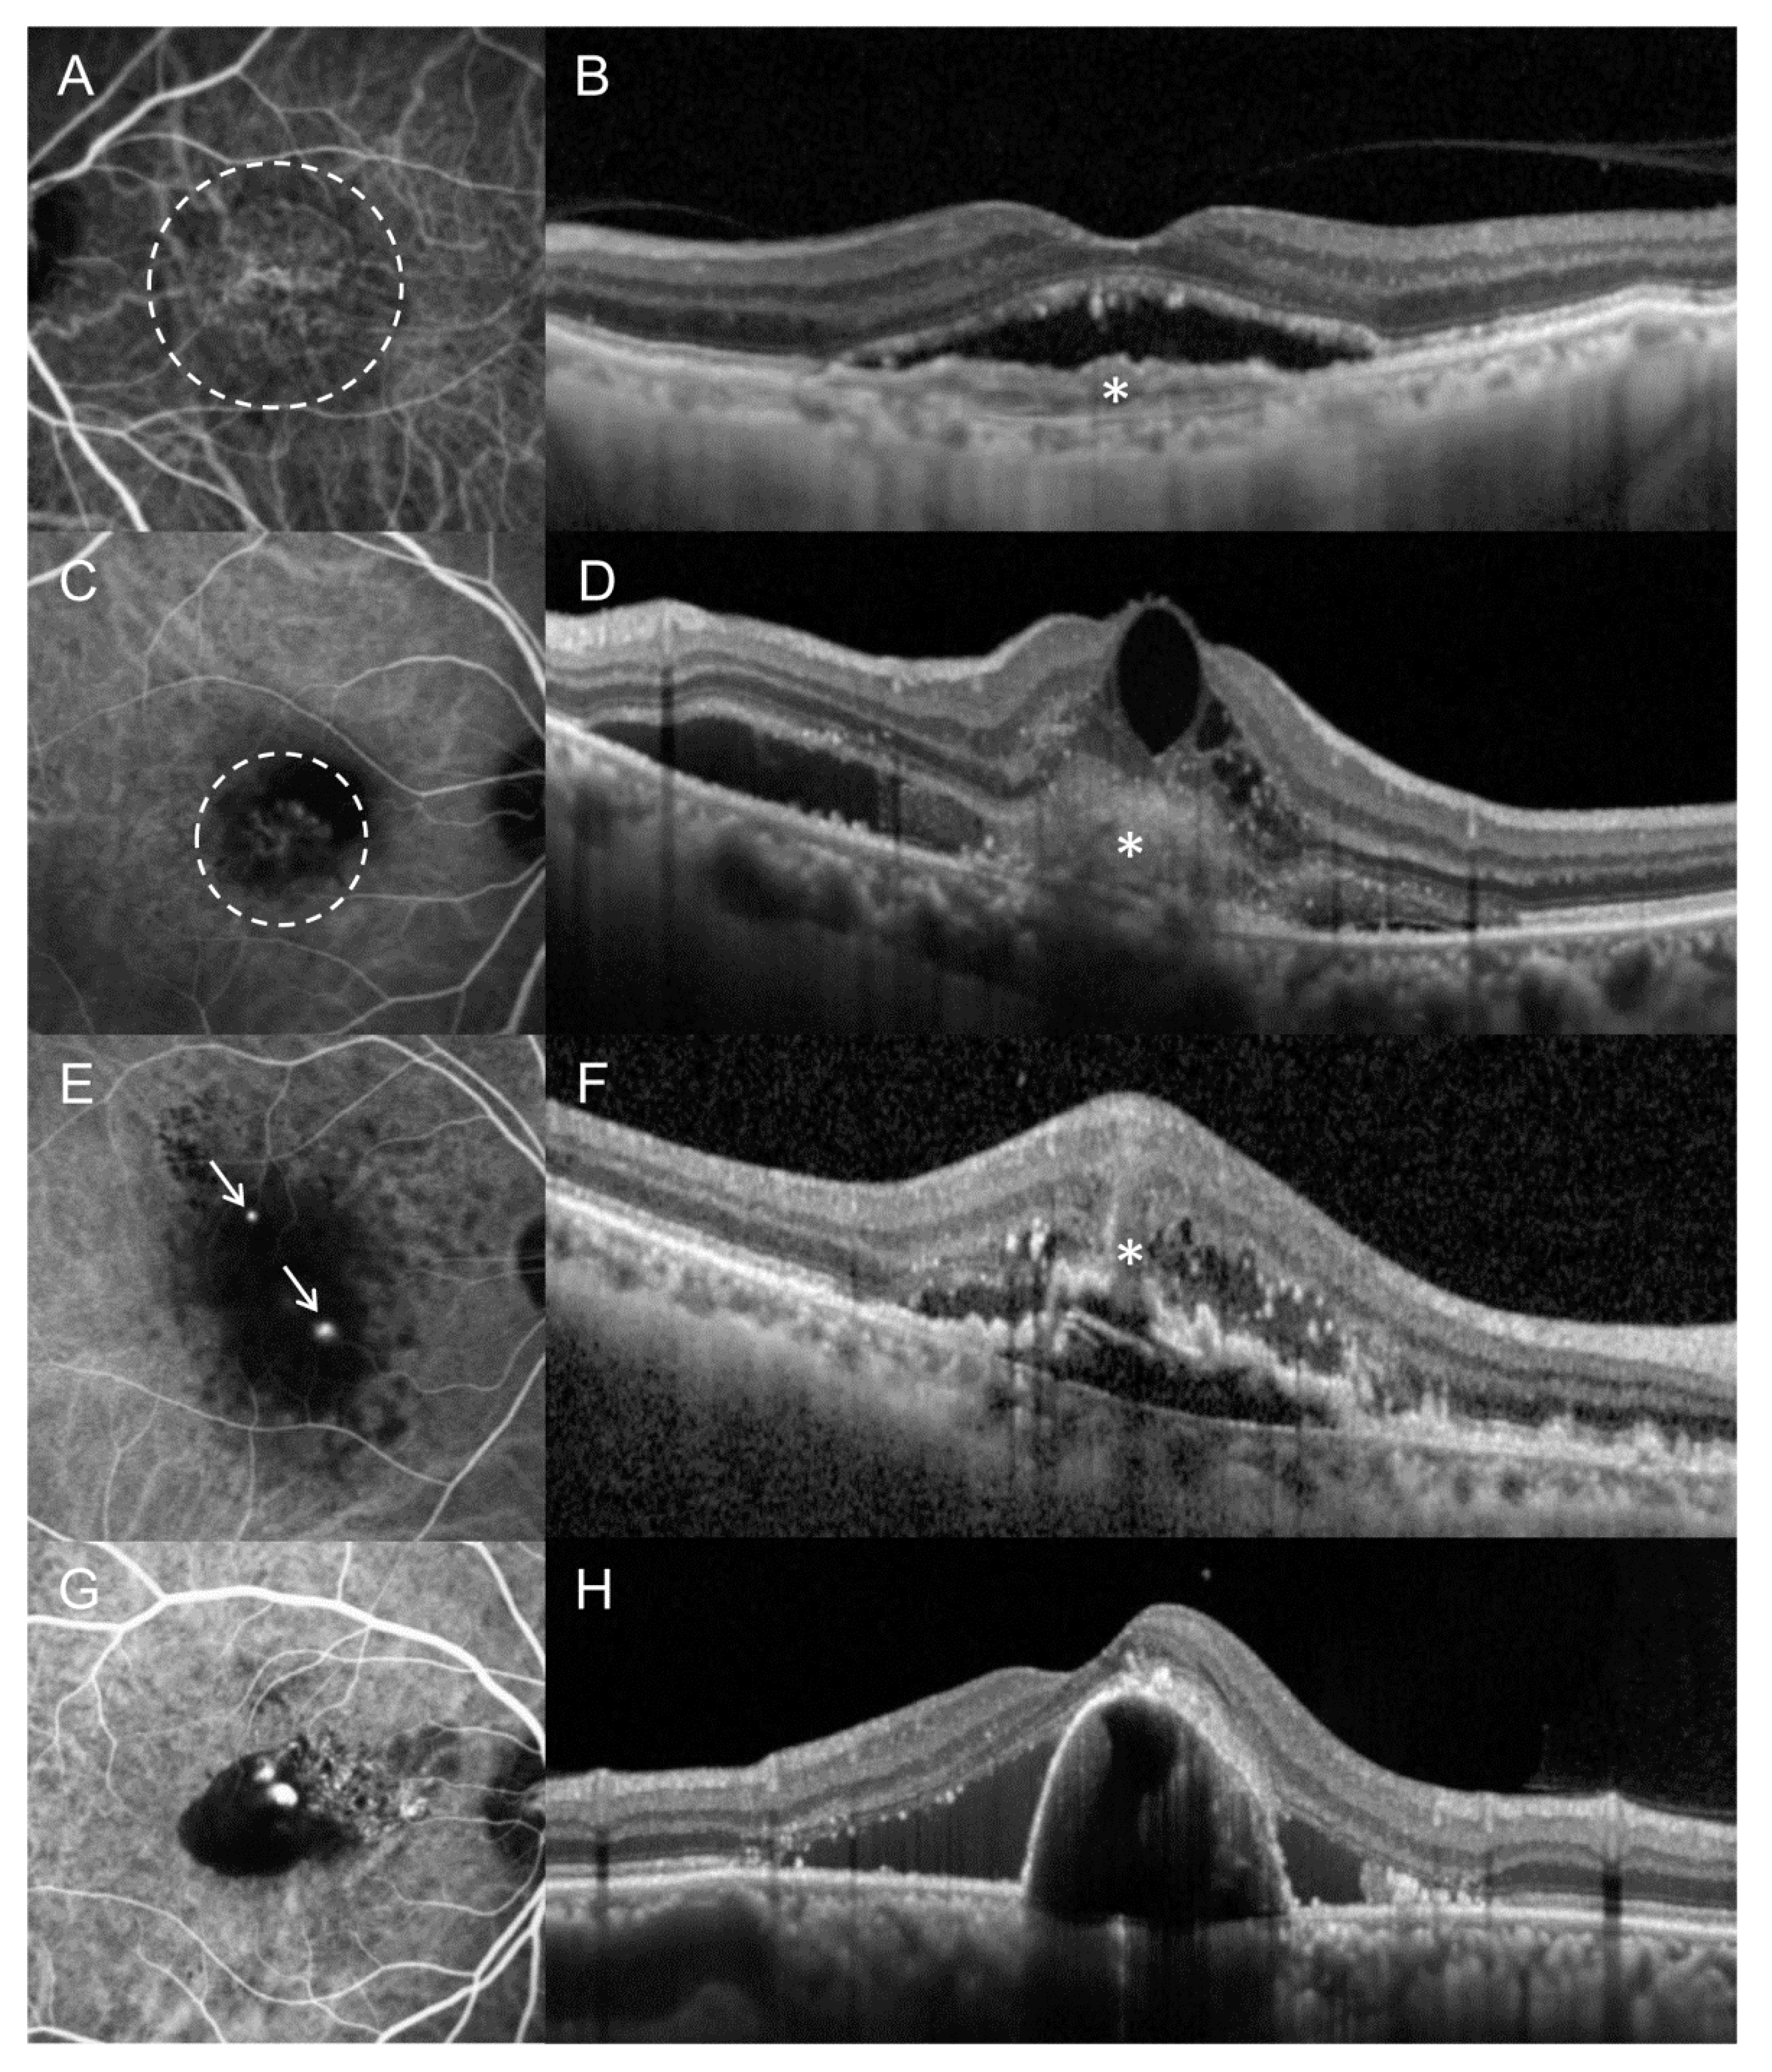

2.2. Classification of Subtypes of MNV